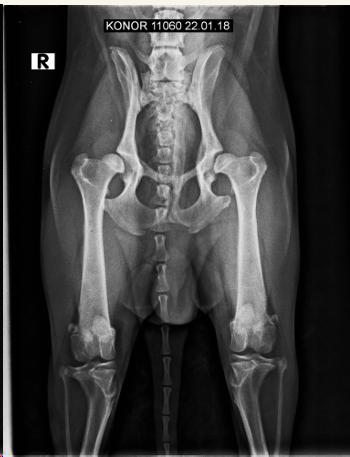

En general se hacen proyecciones:

- Ventro-dorsal: Extender extermidades y traccionar, sin rotación axial, paralelas a la mesa, buscamos que la rotula se superponga con el surco troclear. Posicion de rana si es una fractura pelvica

- Latero-Lateral: Esponja de gomaespuma entre rodillas, estirar extermidades posteriores a caudal

Displasia de cadera:

- Más en perro que en gato

- Pasa de Laxitud articular a subluxación a EDA secundaria

- Incluir la pelvis, femur y rotulas en radiografia.

- Signos radiográficos típicos según el grado ( A---E ) Siendo A un animal sano y E una enfermedad muy avanzada